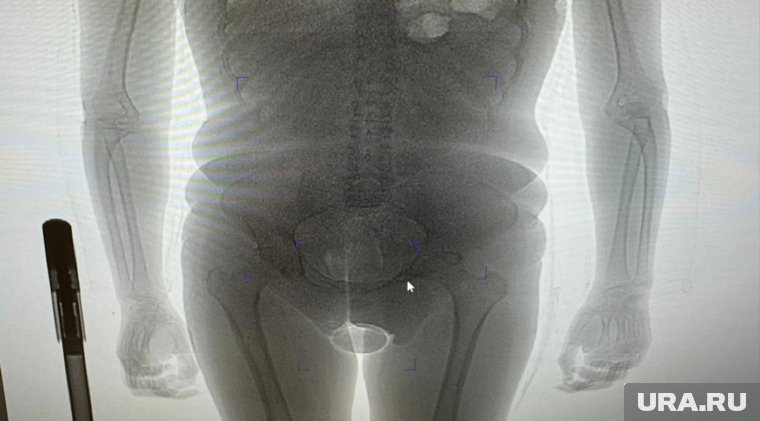

«В результате проведения таможенного досмотра обнаружено два презерватива с порошкообразным веществом внутри, один из которых находился в нижнем белье пассажирки, второй сокрыт внутриполостным способом», — говорится в заявлении пресс-секретаря. Информация есть в распоряжении URA.RU.

Девушка пояснила, что вещество представляет собой кокаин, который она согласилась перевезти по просьбе неустановленного мужчины за денежное вознаграждение. Проведенная экспертиза подтвердила, что изъятое вещество является кокаином общей массой 250 граммов. Сейчас иностранка заключена под стражу. В отношении нее возбуждено уголовное дело по статье о контрабанде наркотических средств в особо крупном размере. Санкция данной статьи предусматривает лишение свободы на срок от 15 лет до пожизненного заключения с возможным штрафом до одного миллиона рублей.